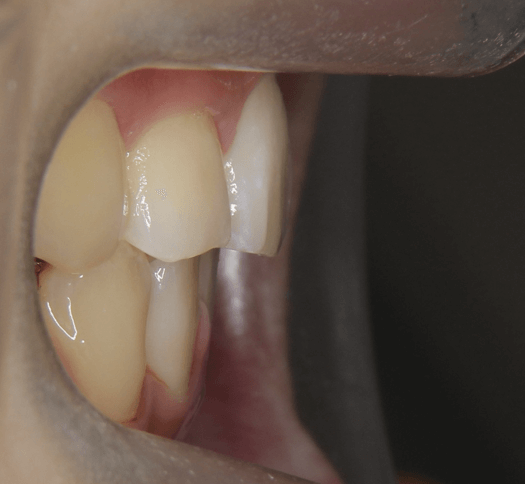

上歯前突+叢生症例 成長期

主訴 | 口元の突出感と歯並びが気になり、将来的な咬合状態を整える目的で来院された患者様です。 |

---|---|

診断結果 | 11歳1か月の女性。骨格的には日本人標準に近く、歯性の上顎前突および叢生が認められました。上下顎ともに歯列のスペース不足があり、永久歯の萌出や歯列の整列に支障をきたす可能性があると診断されました。 |

治療内容 |

|

治療後の経過 | 動的治療終了後は、上下顎の歯列が整い、口元の突出感と叢生が改善されました。審美的・機能的なバランスが取れた状態となり、現在は取り外し式リテーナーを使用し、保定期間に移行しています。 |

治療期間 | 動的治療期間:2年6か月 通院回数:25回 |

治療費用 | 720,000円 |